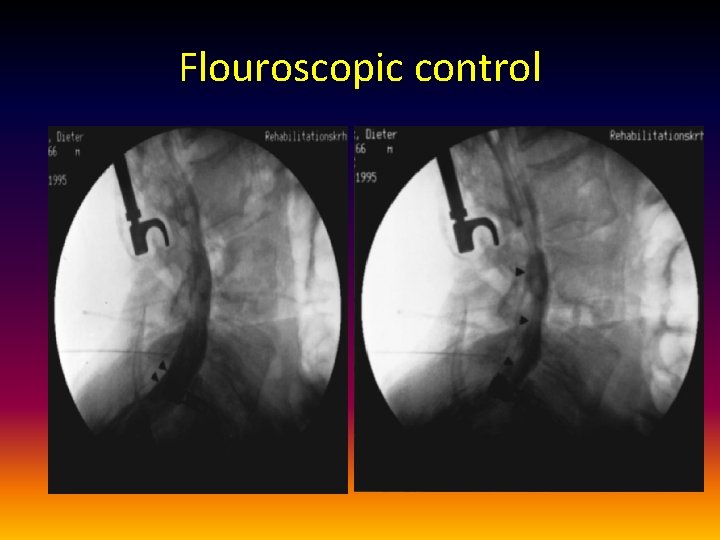

Flouroscopic control